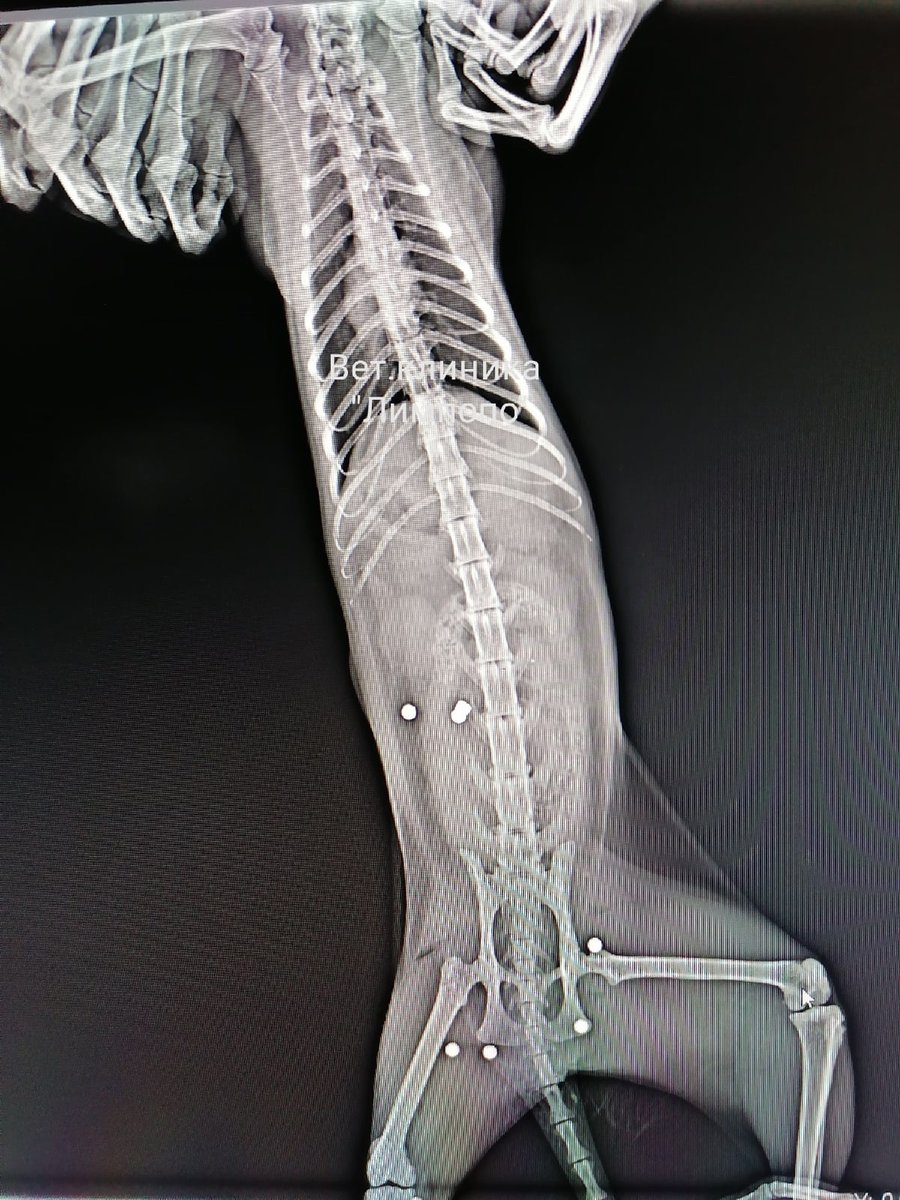

А первая пуля ранила

А первая пуля ранила 109 фото